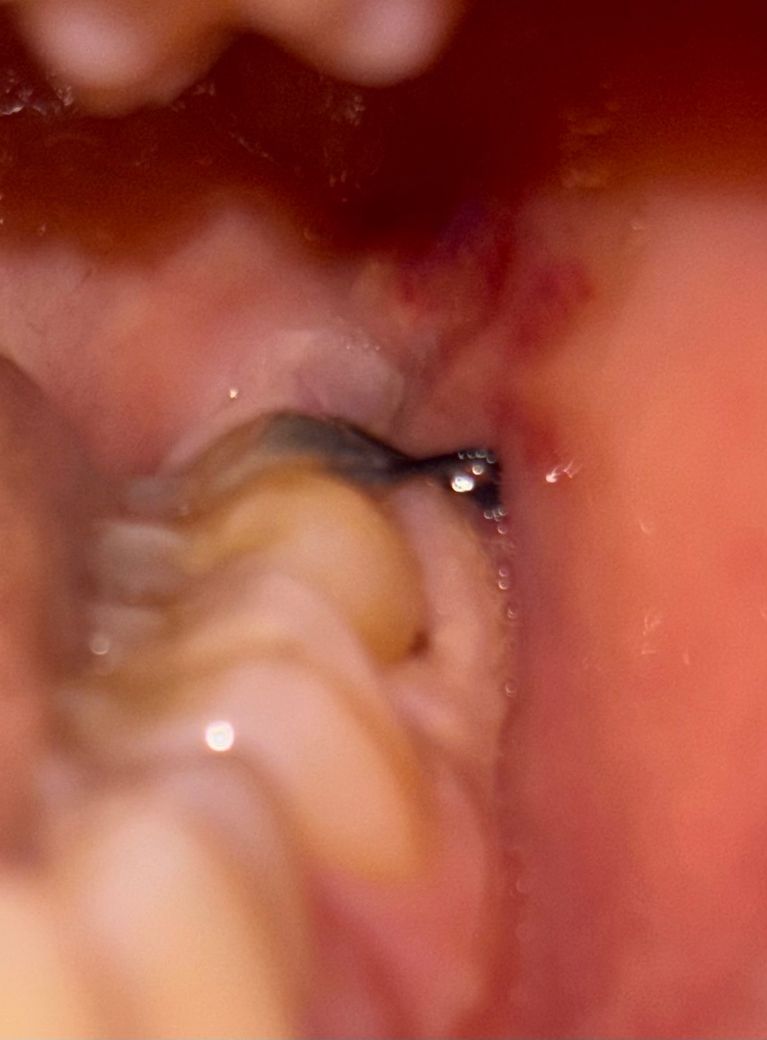

사랑니 발치 후 잇몸이 하얗게 변했어요

3일차에 음식물찌꺼기처럼 어금니와 잇몸 틈새에 흰색덩어리?가 있길래 소독한 면봉으로 살살 떼어냈더니 피가 나더라구요..?ㅠㅠ 그래서 그 뒤로는 거의 건들지 않고 방치했는데, 5일차인 오늘 아침에 봤을때보다 지금 정체모를 흰색덩어리?로 어금니와 잇몸 틈새 대부분이 덮였어요ㅠㅠ 도대체 정체가 무엇인가요?? 뜯어도 되는건가요…?ㅠㅠ 저번처럼 피날까봐 무서워요…

(생각해보니 오늘 아침에 일어났을때부터 실밥도 어제보다 풀린것같이? 되어있었고, 붓기도 갑자기 다시 생겼어요ㅠ)

• 2번 째 사진